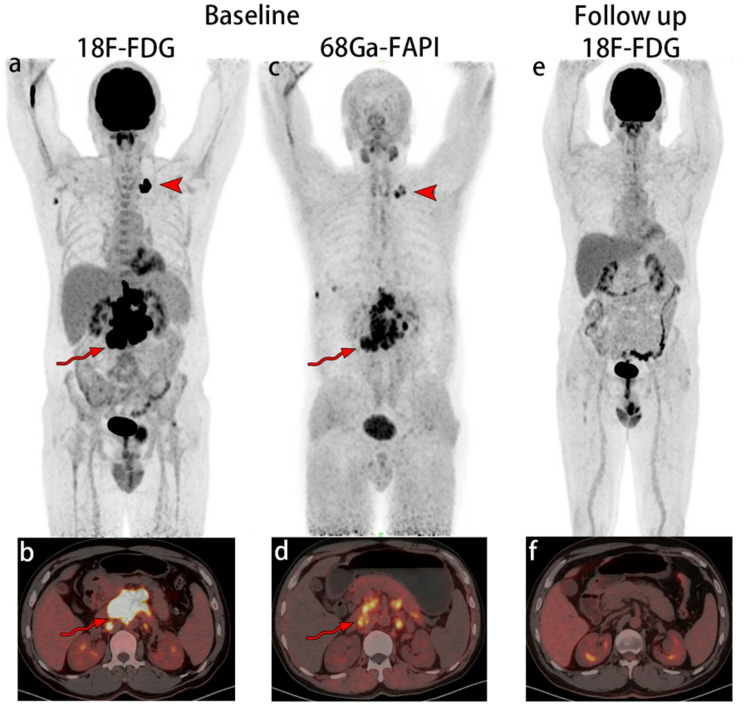

Background: The aim of this study was to investigate the prediction value of metabolic response using gallium 68 (68Ga) labeled fibroblast-activation protein inhibitor (68Ga-FAPI) positron emission tomography-computed tomography (PET/CT) in Non-Hodgkin lymphoma (NHL) patients receiving (cyclophosphamide-doxorubicin HCl-vincristine[Oncovin]- prednisone) CHOP-like chemotherapy.

Method: This single-center prospective study was conducted in our hospital and enrolled participants who was initially diagnosed with NHL and received CHOP-like chemotherapy. 68Ga-FAPI PET/CT was performed before chemotherapy. Metabolic response was assessed by fluorine 18 (18F) labeled fluorodeoxyglucose (18F-FDG) PET/CT. Quantitative analysis included measurement of the maximum standardized uptake value (SUVmax), mean standardized uptake value (SUVmean), peak standardized uptake value (SUVpeak), metabolic tumor volume (MTV) and total lesion FAP (TLF). The SUVmax value of the lesion is divided by SUVmean of normal tissue to calculate the target-to-background ratio (TBRblood and TBRmuscle). Depending on the response, participants were categorized as responders and non-responders. Mann-Whitney U-test was used to compare the 68Ga-FAPI PET/CT parameters of responders with that of non-responders. Logistic regression analyses were performed to determine the relationship between clinical characteristics, 68Ga-FAPI PET/CT parameters, and efficacy of chemotherapy. Receiver operating characteristic curve analysis was used to identify the accuracy of 68Ga-FAPI PET/CT parameters for response prediction.

Conclusion: Low radiotracer uptake on 68Ga-FAPI PET/CT indicated poor metabolic response of NHL patients received CHOP-like therapy. SUVmax could be used to screen sensitive patients.